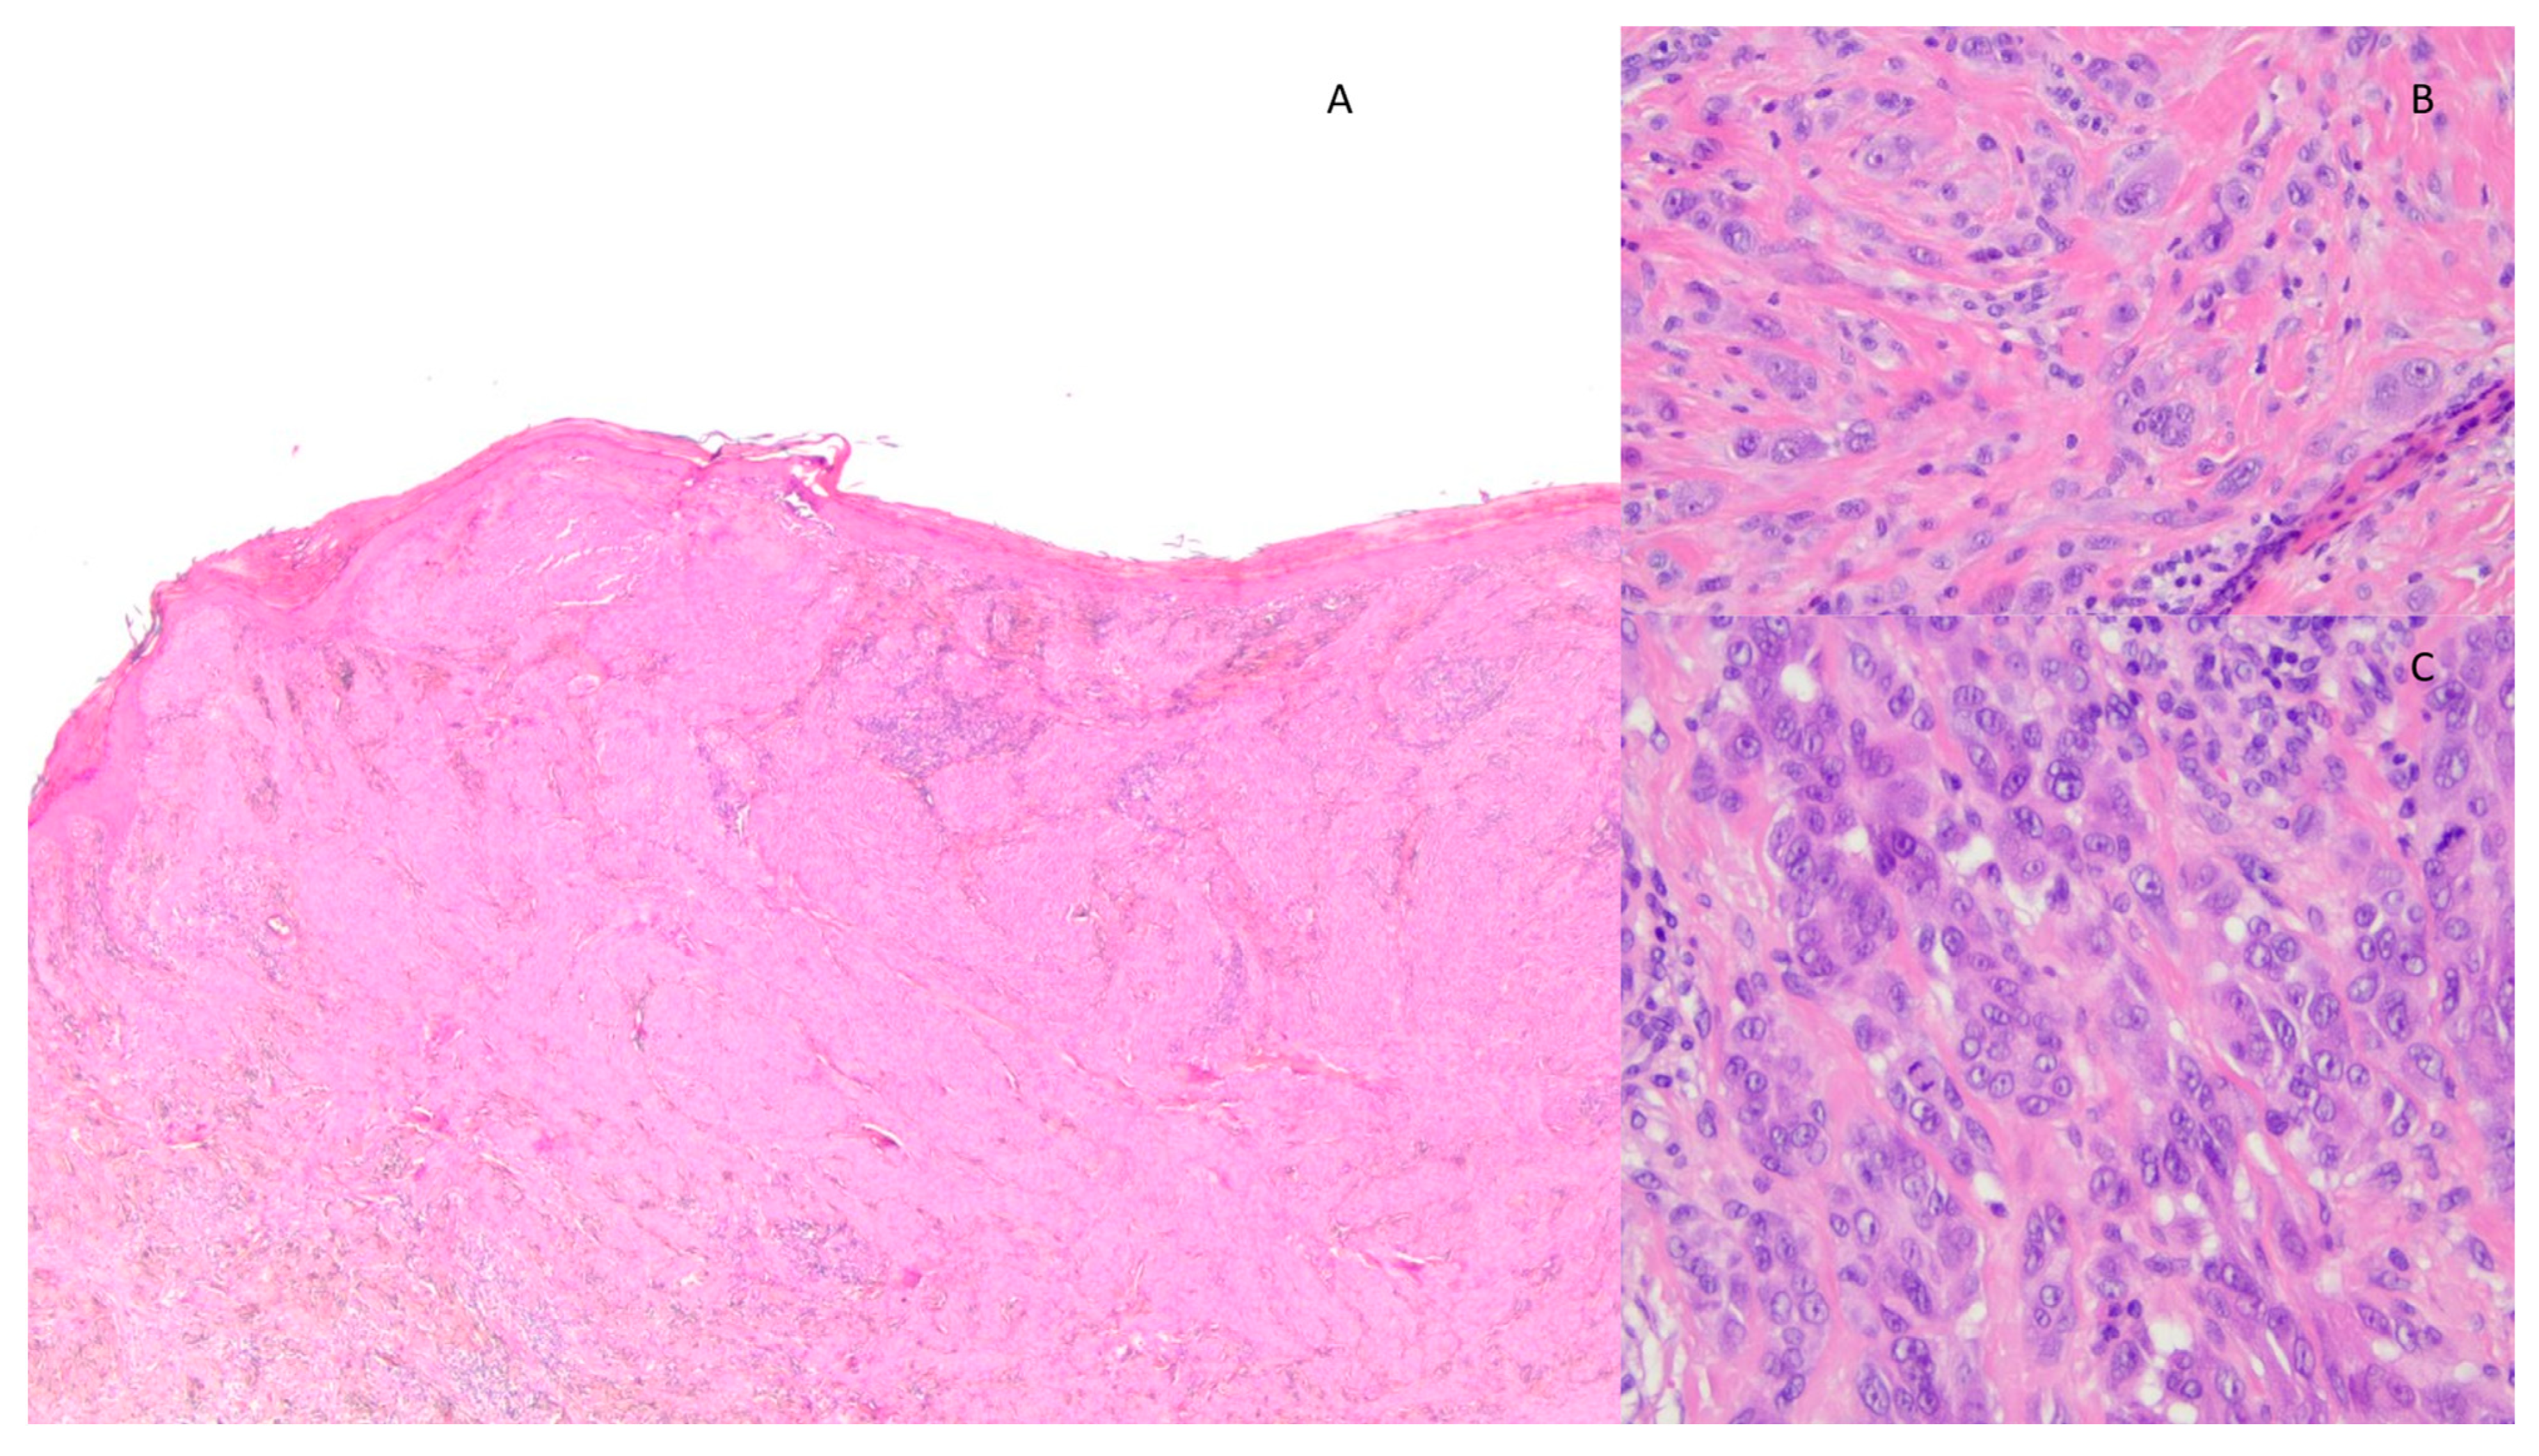

3. Results

4. Discussion